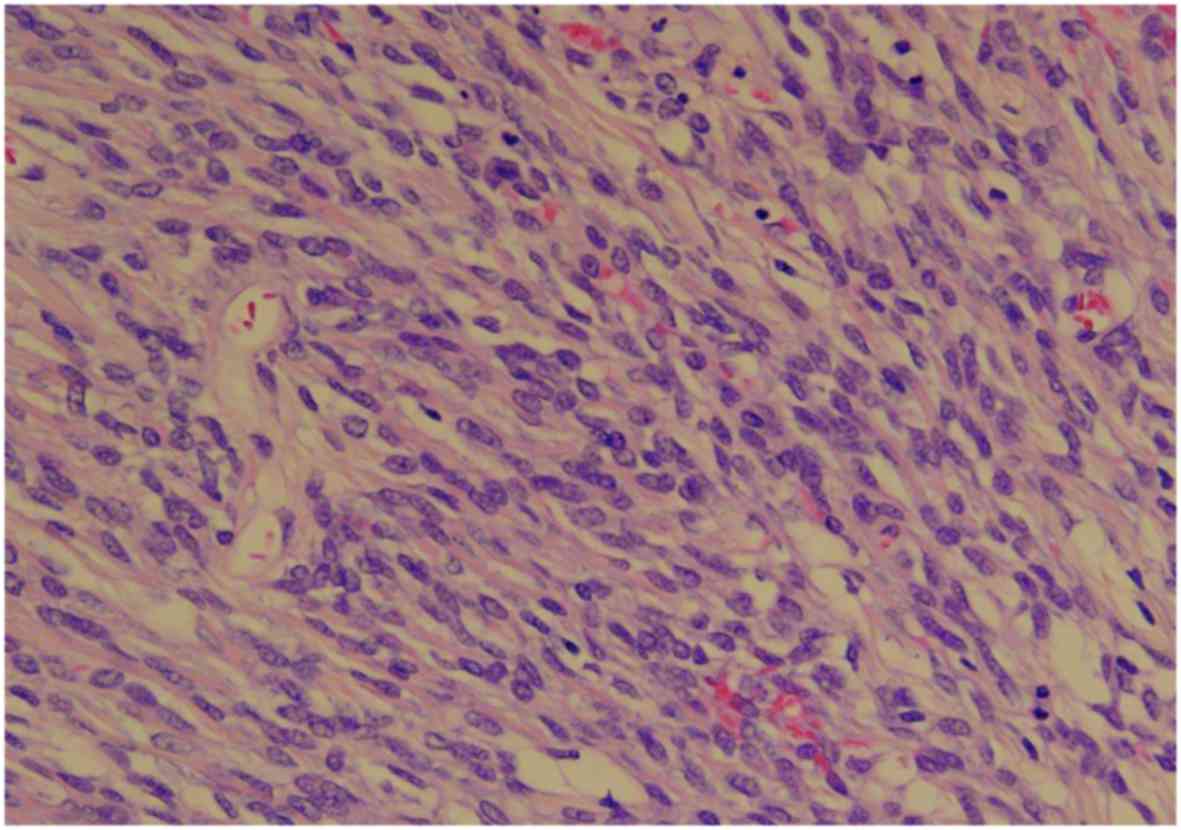

A 51-year-old multigravida woman who experienced abdominal distension for 4 months was referred to the Department of Obstetrics and Gynecology of the Hashimoto Municipal Hospital (Hashimoto, Japan) in April 2014. The patient had no history of lower abdominal or pelvic discomfort, pelvic surgery, or other relevant medical conditions. Transvaginal and transabdominal ultrasound examinations revealed a large solid abdominal mass, which exhibited iso-echogenicity. Magnetic resonance imaging (MRI) revealed a large heterogeneous mass with an irregular component occupying the lower abdominal cavity, with an intact uterus. Based on these radiological findings, the mass was suspected to be an ovarian malignancy (Fig. 1). The results of a laboratory analysis of the patient's peripheral blood revealed normal tumor marker levels [cancer antigen (CA)125, CA19-9 and carcinoembryonic antigen] and an elevated lactate dehydrogenase level (291 IU/l). Total abdominal hysterectomy and bilateral salpingo-oophorectomy were planned. Intraoperative examination revealed a solid mass arising from the lower omentum. The resected mass was 12.5×10.0×7.2 cm in size and weighed 502 g. The consistency of the mass was elastic-hard and partially soft, and its cut surface was whitish-yellow and contained a cystic and necrotic component measuring 2 cm in diameter. Microscopically, the tumor included a well-circumscribed region composed of hyaline-fibrous and mucinous-myxomatous components. The hyaline-fibrous region exhibited diffuse proliferation of spindle-shaped and small round tumor cells, with capillaries arranged in a spider's web-like pattern (Fig. 2). The mucinous-myxomatous region was composed of highly cellular tissue, which displayed a high nuclear:cytoplasmic ratio and mitotic figures. Immunohistochemistry revealed positive staining of the tumor cells for B-cell lymphoma (Bcl)-2, and partially positive staining for CD99 and epithelial membrane antigen (EMA). The tumor cells were negative for S100, α-smooth muscle actin (SMA), desmin, CD34, CD31, cytokeratin (CK)7 and CK AE1/3. The Ki-67 labeling index was 40–60%. Immunohistochemistry helped to exclude leiomyosarcoma, malignant schwannoma, gastrointestinal stromal tumor and solitary fibrous tumor. Although a qualitative analysis of mRNA expression based on a reverse transcription polymerase chain reaction (RT-PCR) assay was performed using an RNA sample extracted from formalin-fixed paraffin-embedded tumor tissue, the SYT-SSX fusion gene transcript was not detected. The diagnosis of primary omental poorly differentiated synovial sarcoma was confirmed based on the pathological findings. The patient's postoperative course was uneventful, and she was discharged from the hospital on postoperative day 7. The patient was treated with a combination of doxorubicin and ifosfamide as adjuvant chemotherapy. Despite normal findings on physical examination, 7 months after the operation a metastatic tumor was detected in the liver by positron emission tomography-computed tomography (PET-CT), and laparoscopic partial liver resection was performed, followed by adjuvant pazopanib. Twelve months after the operation, another metastatic tumor was detected in the liver by PET-CT, and the patient was again treated with laparoscopic partial liver resection followed by adjuvant pazopanib. At 14 months after the first operation, PET-CT revealed multiple recurrent metastatic tumors in the liver, lungs and pleura. Although the patient was treated with partial lung resection, aggressive metastatic tumors were detected in the liver, lungs and abdominal cavity at 2 months after the first operation. Due to the difficulty of surgical resection, the patient was treated with trabectedin, and she remained alive with stable disease at 24 months after the first operation. The patient provided written informed consent regarding the publication of the case details and associated images.

Figure 2.

Hematoxylin and eosin staining of omental synovial sarcoma, showing diffuse proliferation of spindle-shaped and small round tumor cells (magnification, ×100).

Histologically, poorly differentiated synovial sarcoma is formed from sheets of undifferentiated round cells with hyperchromatic nuclei, which exhibit frequent mitoses, whereas biphasic synovial sarcoma is composed of a combination of epithelial and spindle cell components, and monophasic synovial sarcoma is diagnosed when only an epithelial or a spindle cell component is observed (1). Immunohistochemical studies may confirm the pathological diagnosis. Poorly differentiated synovial sarcoma is usually positive for Bcl-2 and CD99, and focally positive for EMA, but it is negative for S-100, α-SMA, desmin, CD34 and CD31. Poorly differentiated synovial sarcoma differs from biphasic or monophasic synovial sarcoma in that it is also negative for CK7 and CK AE1/3, which emphasizes its poorly differentiated status and the non-epithelial nature of the tumor cells. The SYT-SSX fusion gene, which is produced by the chromosomal translocation t(X;18)(p11.2;q11.2), is found in ~90% of synovial sarcomas during fluorescence in situ hybridization or RT-PCR analysis of the gene transcript (7). Although previous studies have detected the SYT-SSX fusion gene in omental synovial sarcoma (2,3), its true frequency in omental poorly differentiated synovial sarcoma remains unknown. Even if molecular testing for the SYT-SSX fusion gene produces a negative result, the diagnosis of synovial sarcoma may be confirmed based on immunohistochemical findings. While the product of the SYT-SSX fusion gene was not detected in the present case, immunohistochemistry detected positivity for Bcl-2, focal positivity for CD99 and EMA, and negativity for S100, α-SMA, desmin, CD34, CD31, CK7 and CK AE1/3. Thus, a final diagnosis of poorly differentiated omental synovial sarcoma was made.